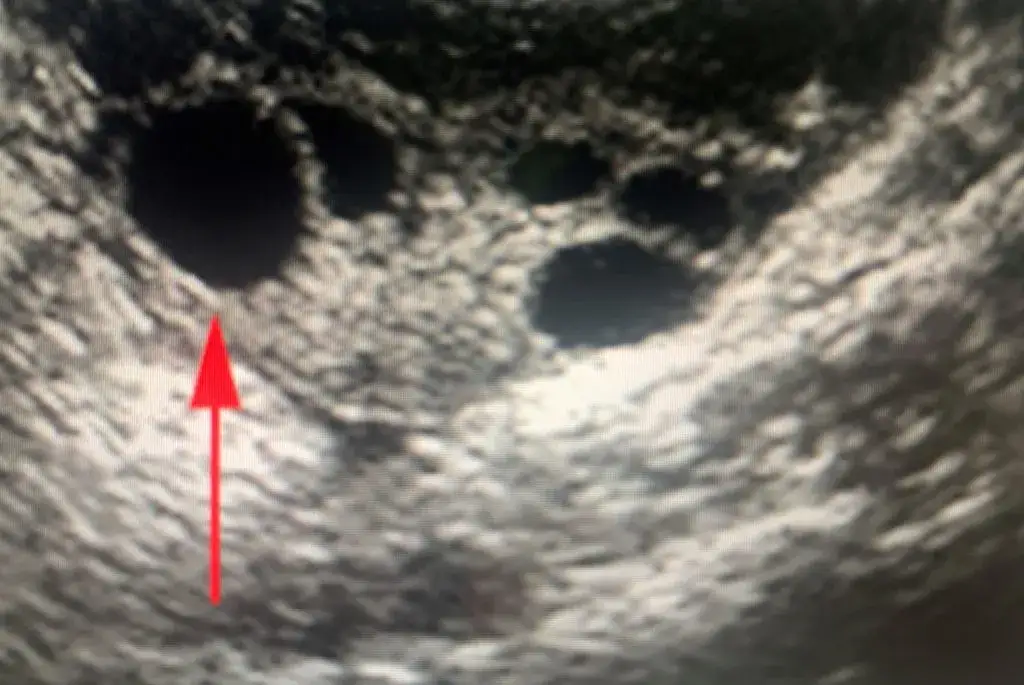

Niepęknięty pęcherzyk Graafa i cykle bezowulacyjne

Jednym z częstych scenariuszy jest sytuacja, gdy w okresie poowulacyjnym w USG nadal widoczny jest duży, niepęknięty pęcherzyk. Zamiast pęknąć i uwolnić komórkę jajową, pęcherzyk ten może nadal rosnąć i przekształcić się w tzw. torbiel prostą (czynnościową). Taki stan świadczy o braku owulacji, czyli o cyklu bezowulacyjnym. Co ciekawe, czasem taki niepęknięty pęcherzyk może ulec luteinizacji, czyli zacząć produkować progesteron, ale bez uwolnienia komórki jajowej to zjawisko nazywamy syndromem LUF (Luteinized Unruptured Follicle, czyli pęcherzyk luteinizujący bez pęknięcia). W obu tych przypadkach, kluczowe jest, że nie stwierdzam obecności ciałka żółtego ani płynu w zatoce Douglasa, co jednoznacznie wskazuje na brak owulacji.

- Brak pękniętego pęcherzyka dominującego: Zamiast niego widoczny jest duży, niepęknięty pęcherzyk, który może przekształcić się w torbiel.

- Brak ciałka żółtego w jajniku: To kluczowy wskaźnik. Jeśli owulacja nie nastąpiła, ciałko żółte nie ma szans się uformować.

- Brak wolnego płynu w zatoce Douglasa: Skoro pęcherzyk nie pękł, nie ma płynu pęcherzykowego, który mógłby się tam zgromadzić.